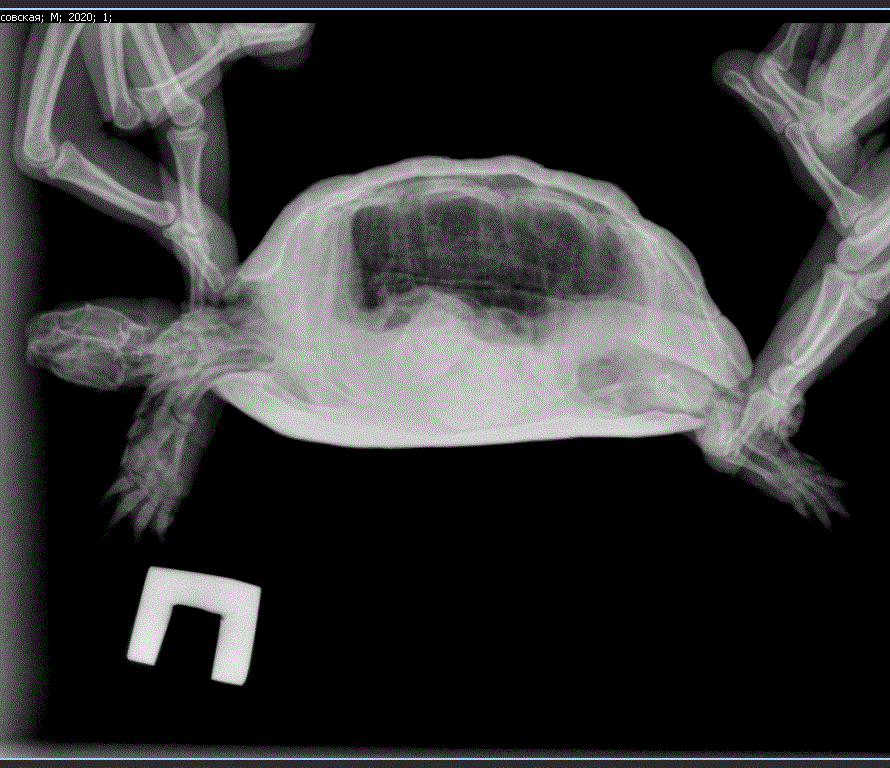

@Светлана Мур Константин сказал сделать рентген дорсовентральная и правая латеральная проекции. Вот список по Ярославлю где могут осмотреть/сделать https://cherepahi.ru/web/spravka/1194-spravochnik-yaroslavl

@moth Добрый вечер. Съездили на рентген. Герпетолог сейчас в декрете, поэтому принимает только по записи. Я решила быстрее сделать рентген.

Что скажете? Могу записаться на платную консультацию к герпетологу на сайте, если это необходимо. Либо записаться к нашему в клинике, если она примет в ближайшее время.

Я сохранила снимки в виде фото для наглядности, а так же вот ссылка на снимки и программу для просмотра. Там можно яркость и контрастность менять.

https://drive.google.com/drive/folders/14HY6nSz0MGbUpkHyCgvYg6a1Utd932dq?usp=sharing

@Светлана Мур Константин ответил, что в целом всё нормально, есть небольшой завал кишечника. Сказал давать кальций не размачивая, т.к. он может прилипать/засыхать где-то во рту и черепаха таким образом пытается от неё избавиться.